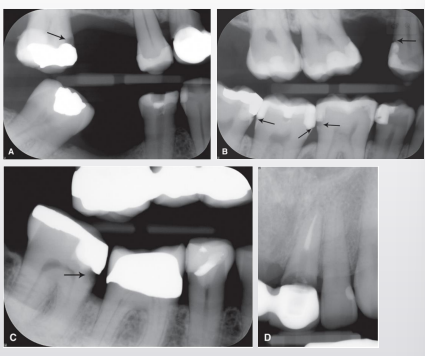

misinterpretation of cervical burnout

what is cervical burnout

artifact that can mimic caries commonly at or just apical to CEJ near alveolar crest

what is the cause of cervical burnout

x-rays passing tangentially through proximal area encounter less structure; shallow depression/concavity on M/D root surface can make area appear more radiolucent

when thinking of cervical burnout, thinner tooth structures absorbs fewer x-rays, so it will appear more ________________ (radiopaque/radiolucent) on the radiograph

radiolucent

caries or cervical burn out

burnout

caries or cervical burnout

caries